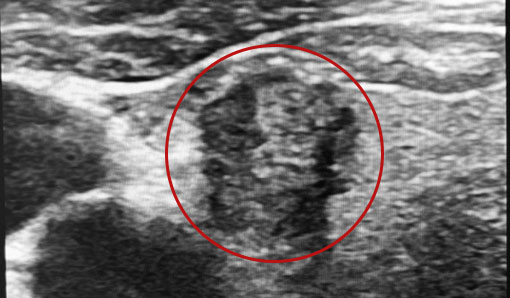

甲状腺がんのエコー画像

甲状腺とは?

のどぼとけの下にある蝶のような形をした臓器です。

新陳代謝を促進し、脈拍数や体温を調節するホルモンを分泌します。